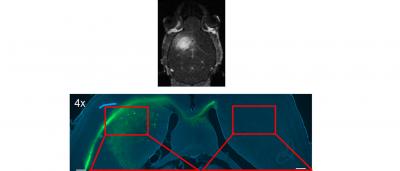

So far, the researchers have proven the efficacy of their technique on mice. They chose a fluorescent molecule called 5-dodecanoylaminofluorescein and confirmed that it was reaching the brain without affecting other parts of the animal. At the same time, they identified the acoustic pressure thresholds from which the substance is guaranteed to reach its target in vivo.